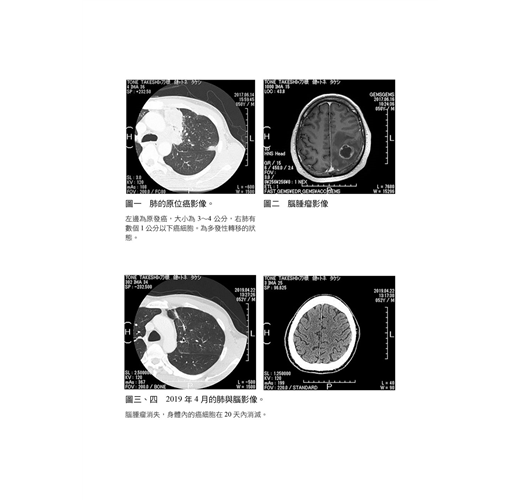

2016年9月1日確診罹患肺腺癌(四期),隔年6月發現癌細胞轉移腦部,當時醫師已經宣告「隨時可能停止呼吸」。後接受精密檢查發現,癌細胞甚至已轉移至兩眼、左右兩邊肺部、從肺部至頸部的淋巴、肝臟、左右兩邊的腎臟、脾臟、全身骨頭,然而,在絕望中卻出現神祕體驗。在經歷神祕體驗,住院一個月後,奇蹟般地完全康復。至2017年7月底回醫院檢查後,發現體內癌細胞完全消失。現在,在日本各地演講,分享自己從癌末生還的體驗中學習到與察覺到的事物,也將體驗與心情書寫出來分享大眾。